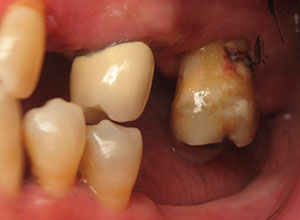

Por otro lado, este tipo de rehabilitación también está indicada en aquellas personas que, aunque aún mantienen dientes en la boca, dichas piezas dentales presentan un pronóstico imposible a corto plazo y están abocados al edentulismo total.

Antes de comenzar a fabricar la prótesis es necesario realizar un completo estudio del caso concreto de cada paciente, para asegurarnos de que ésta se ajusta completamente a sus necesidades (en todo lo relativo a color, tamaño, comodidad, etc).